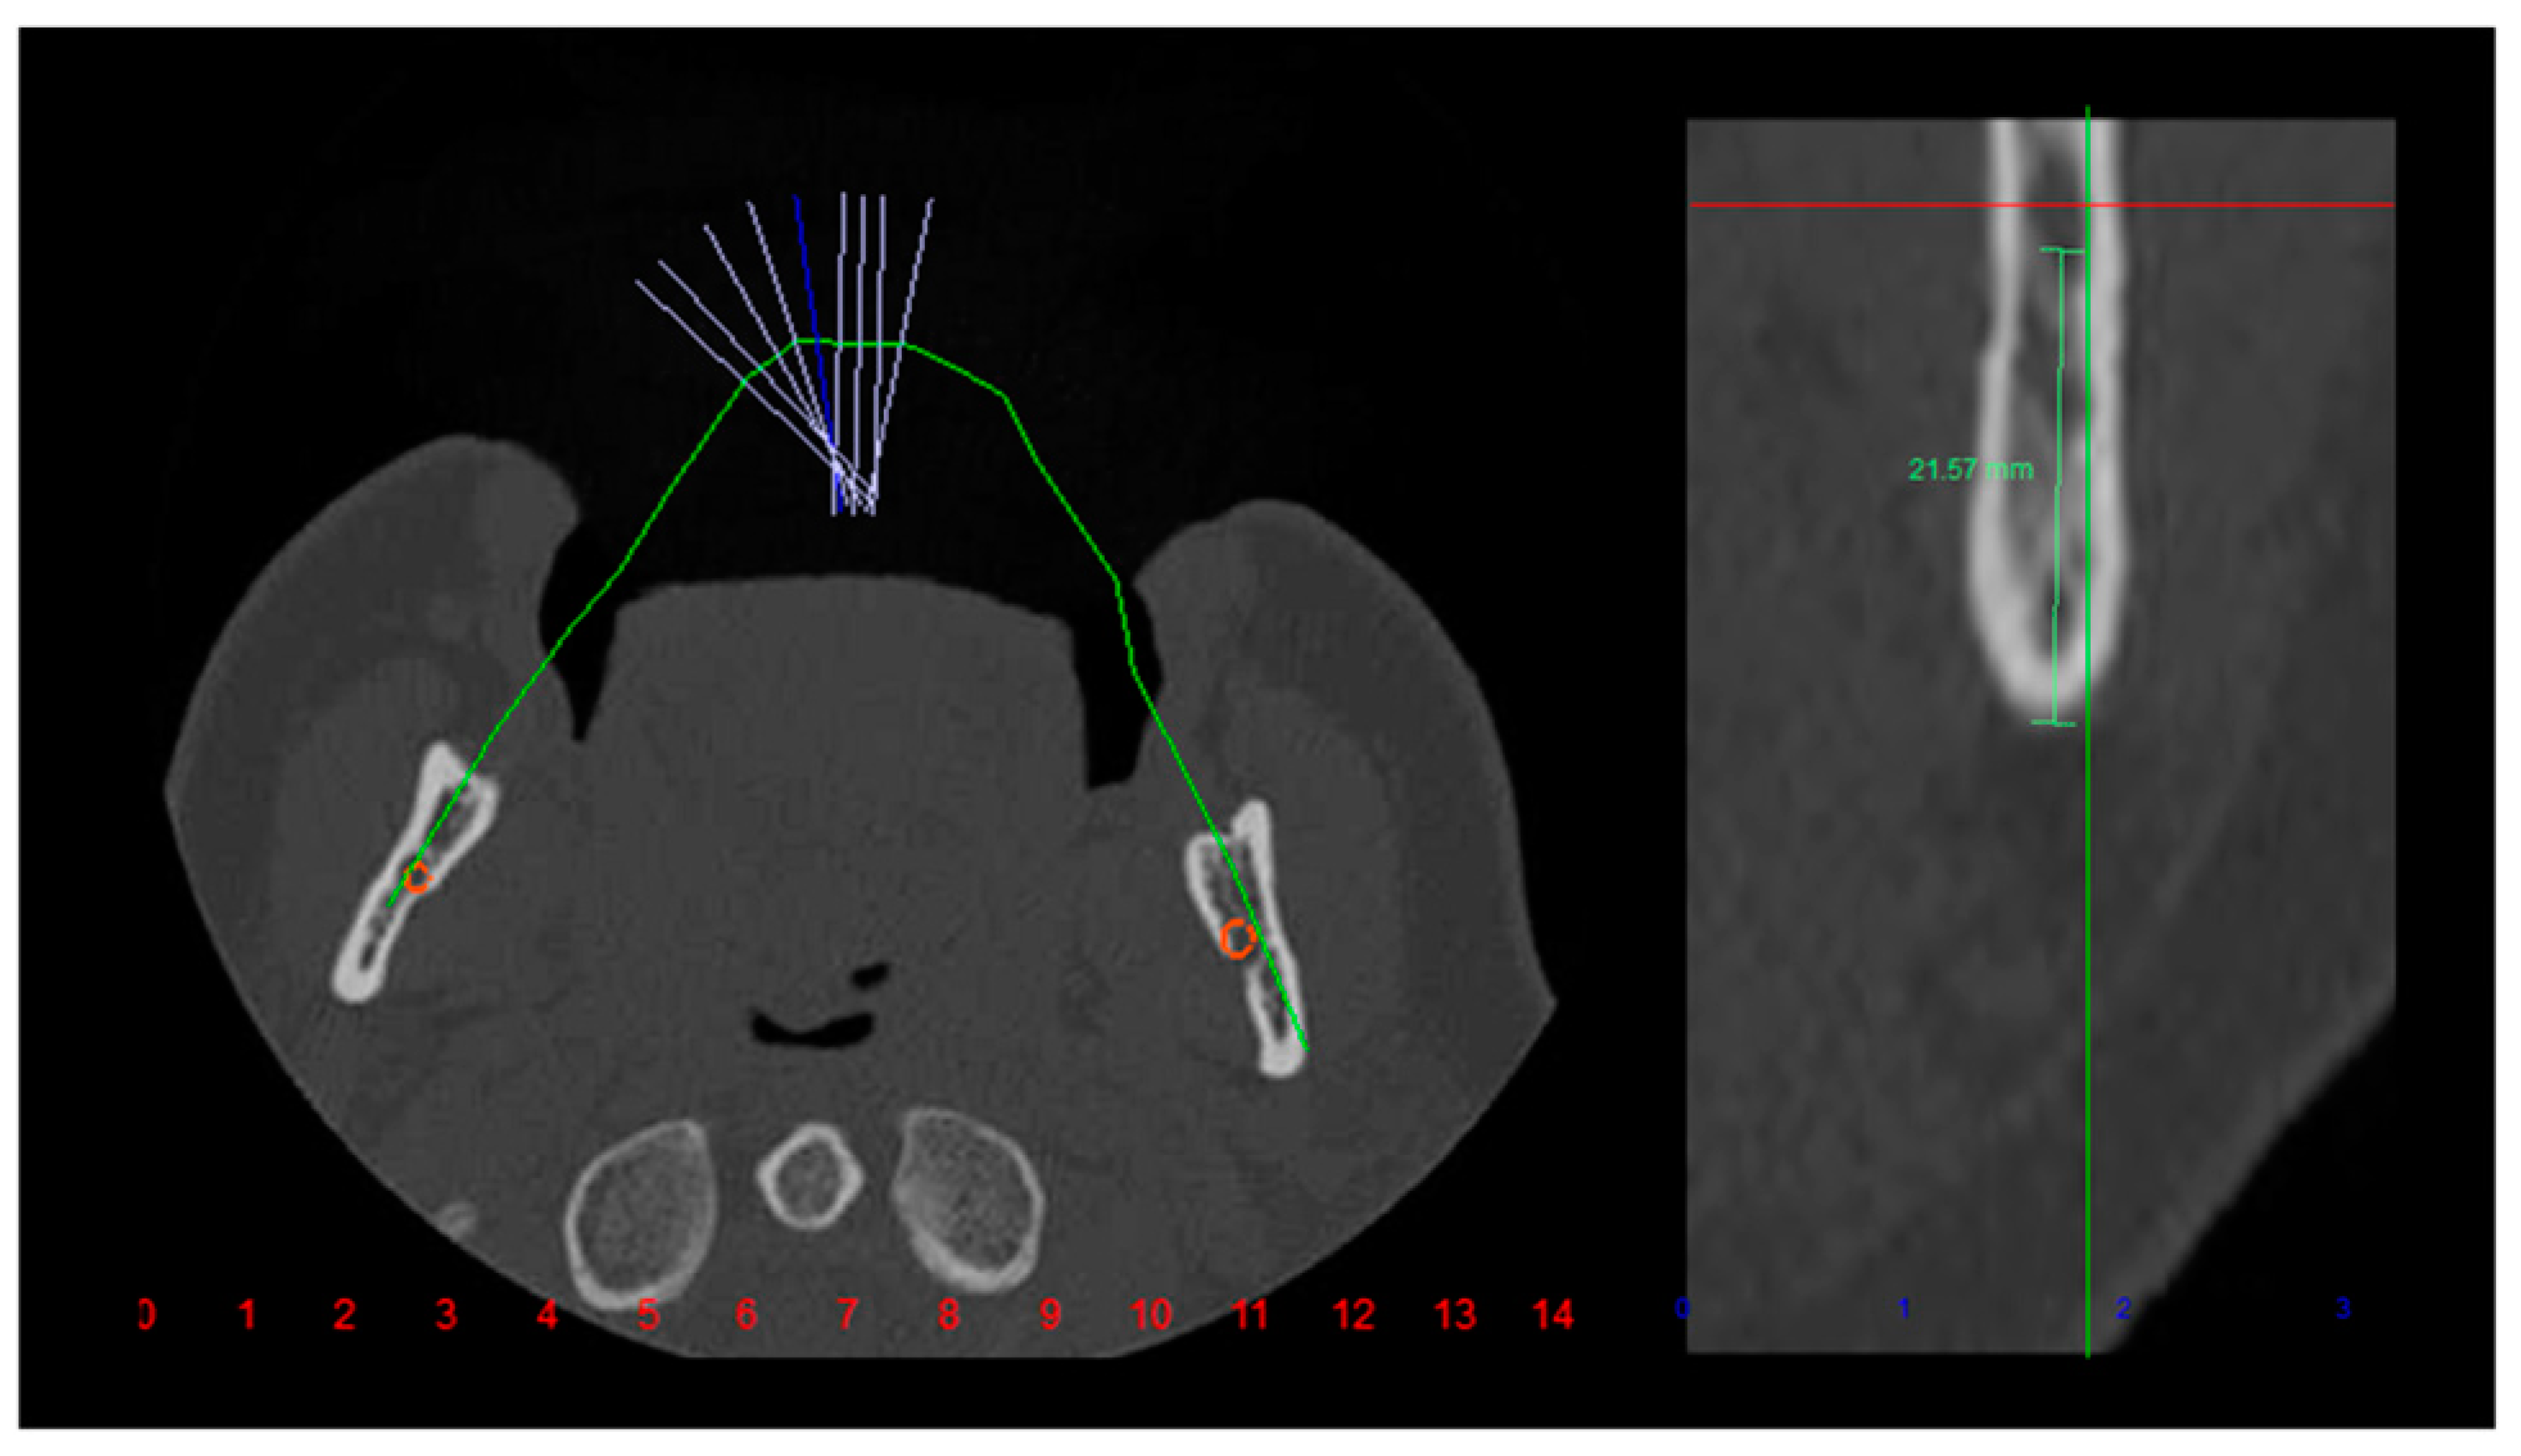

Tomographic Evaluation of Bone Height Between the Mandibular Canal and the Inferior Cortex of the Mandible Related to Bicortical Screws Fixation

Fares, R.D.; Leal, J.V.B.; da Silva Areas, M.Z.; da Rocha, H.V.; de Moraes, S.L.C.; Homsi, N.; da Silva, J.R. Tomographic Evaluation of Bone Height Between the Mandibular Canal and the Inferior Cortex of the Mandible Related to Bicortical Screws Fixation. Craniomaxillofac. Trauma Reconstr. 2024, 17, 181-185. https://doi.org/10.1177/19433875231213892